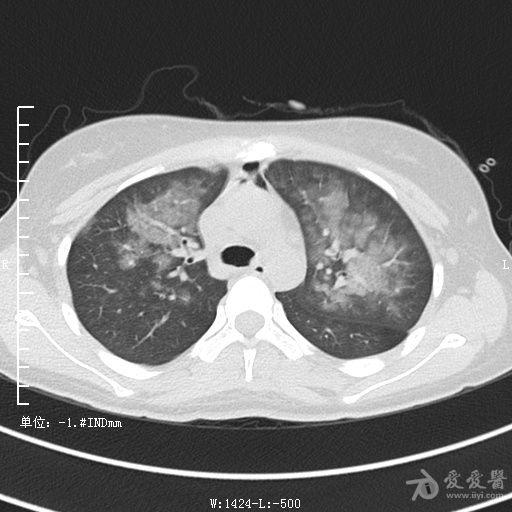

典型支气管扩张及肺水肿CT片

典型支气管扩张肺水肿